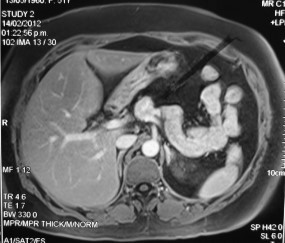

Paciente femenina de 48 años de edad que ingresa a Hospital Sanatorio Franchin por síntomas de cefalea y mareos, cuadro que se hace progresivo, presentando síncopes y posteriormente alteración del estado de conciencia. Los exámenes clínicos revelan una glucosa de 40 mg/dl, concomitante con insulina alta y péptido C elevado. Ingresa de forma programada para realización de duodeno pancreatectomía el 29 de mayo de 2021. Imágenes diagnósticas muestran estudio trifásico de tomografía de abdomen, lesión nodular en la cabeza del páncreas con ávido realce en fase arterial que en resonancia magnética se observa hiperintensa en T2, presenta restricción con la difusión y caída de la señal en el ADC. Además presenta realce tras la administración de contraste con gadolinio.

La resonancia magnética es el otro estudio de imagen no invasivo que nos permite la detección de la lesión con una sensibilidad mayor que la de la tomografía, del 85% al 95%, donde los insulinomas presentan un realce tras la administración de contraste con gadolinio y secuencias T1 sin contraste son lesiones hipointensas y en secuencias T2 son hiperintensas.

La resonancia magnética confirmó aún más el diagnóstico de las lesiones ya previamente visualizadas en tomografía en esta revisión, con realce de las lesiones en secuencias T1 y contraste con gadolinio, y en las secuencias funcionales con restricción de la lesión y caída de la señal en el mapa de ADC.